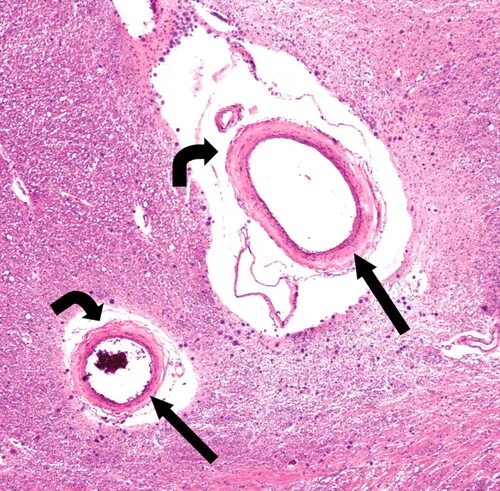

Что значит пространства вирхова робина